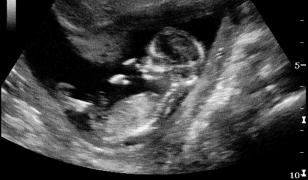

Ecografia de şold reprezintă o metodă neinvazivă de depistare a displaziei de şold, boală cunoscută anterior şi sub numele de luxatie de şold. Specialiştii recomandă ca toţi sugarii să efectueze o ecografie de şold în primele 3 luni de viaţă.

În ţări, precum Germania, Austria, Elveţia, această investigaţie face parte din examinările de rutină ale nou-născutului şi ale sugarului. Este o investigaţie nedureroasa, neinvazivă şi neiradiantă, motiv pentru care poate fi repetată de câte ori este nevoie, fără a pune în pericol sănătatea bebeluşului.